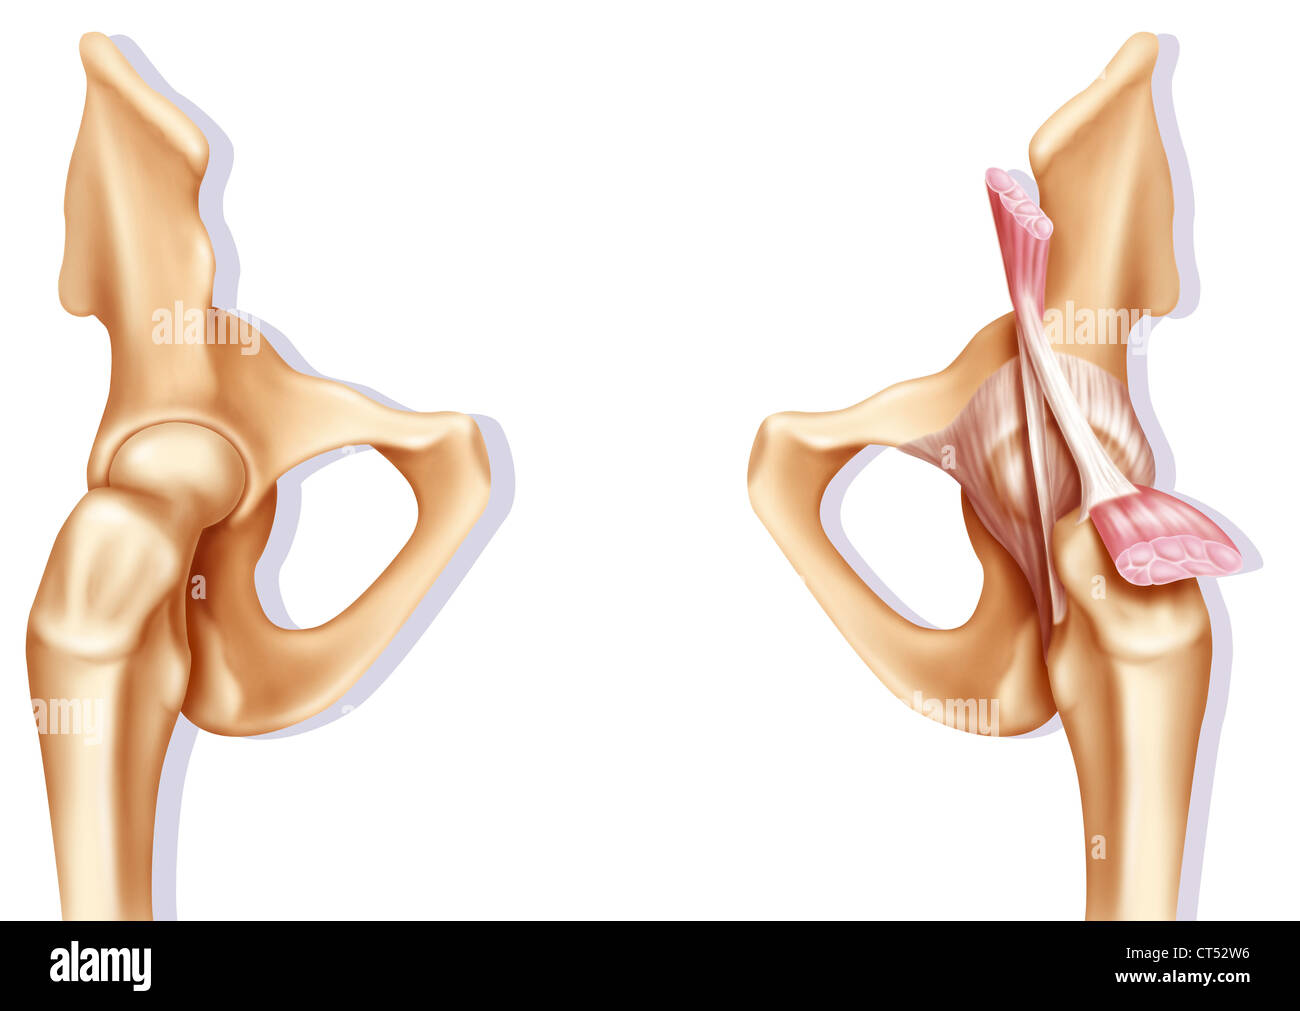

Articulation osseuse de la hanche sans et avec la capsule de l'articulation coxofémorale. Banque D'Imageshttps://www.alamyimages.fr/image-license-details/?v=1https://www.alamyimages.fr/articulation-osseuse-de-la-hanche-sans-et-avec-la-capsule-de-l-articulation-coxofemorale-image476923594.html

Articulation osseuse de la hanche sans et avec la capsule de l'articulation coxofémorale. Banque D'Imageshttps://www.alamyimages.fr/image-license-details/?v=1https://www.alamyimages.fr/articulation-osseuse-de-la-hanche-sans-et-avec-la-capsule-de-l-articulation-coxofemorale-image476923594.htmlRF2JKWMWE–Articulation osseuse de la hanche sans et avec la capsule de l'articulation coxofémorale.

Anatomie de l'articulation coxofémorale (hanche) avec les muscles, les tendons. Banque D'Imageshttps://www.alamyimages.fr/image-license-details/?v=1https://www.alamyimages.fr/anatomie-de-l-articulation-coxofemorale-hanche-avec-les-muscles-les-tendons-image476923600.html

Anatomie de l'articulation coxofémorale (hanche) avec les muscles, les tendons. Banque D'Imageshttps://www.alamyimages.fr/image-license-details/?v=1https://www.alamyimages.fr/anatomie-de-l-articulation-coxofemorale-hanche-avec-les-muscles-les-tendons-image476923600.htmlRF2JKWMWM–Anatomie de l'articulation coxofémorale (hanche) avec les muscles, les tendons.

Anatomie de l'articulation coxofémorale (hanche) avec les muscles, les tendons. Banque D'Imageshttps://www.alamyimages.fr/image-license-details/?v=1https://www.alamyimages.fr/anatomie-de-l-articulation-coxofemorale-hanche-avec-les-muscles-les-tendons-image476923664.html

Anatomie de l'articulation coxofémorale (hanche) avec les muscles, les tendons. Banque D'Imageshttps://www.alamyimages.fr/image-license-details/?v=1https://www.alamyimages.fr/anatomie-de-l-articulation-coxofemorale-hanche-avec-les-muscles-les-tendons-image476923664.htmlRF2JKWN00–Anatomie de l'articulation coxofémorale (hanche) avec les muscles, les tendons.

Articulation osseuse de la hanche sans et avec la capsule de l'articulation coxofémorale. Banque D'Imageshttps://www.alamyimages.fr/image-license-details/?v=1https://www.alamyimages.fr/articulation-osseuse-de-la-hanche-sans-et-avec-la-capsule-de-l-articulation-coxofemorale-image476923691.html

Articulation osseuse de la hanche sans et avec la capsule de l'articulation coxofémorale. Banque D'Imageshttps://www.alamyimages.fr/image-license-details/?v=1https://www.alamyimages.fr/articulation-osseuse-de-la-hanche-sans-et-avec-la-capsule-de-l-articulation-coxofemorale-image476923691.htmlRF2JKWN0Y–Articulation osseuse de la hanche sans et avec la capsule de l'articulation coxofémorale.

Hanche, ILLUSTRATION Banque D'Imageshttps://www.alamyimages.fr/image-license-details/?v=1https://www.alamyimages.fr/photo-image-hanche-illustration-49284514.html

Hanche, ILLUSTRATION Banque D'Imageshttps://www.alamyimages.fr/image-license-details/?v=1https://www.alamyimages.fr/photo-image-hanche-illustration-49284514.htmlRMCT52W6–Hanche, ILLUSTRATION